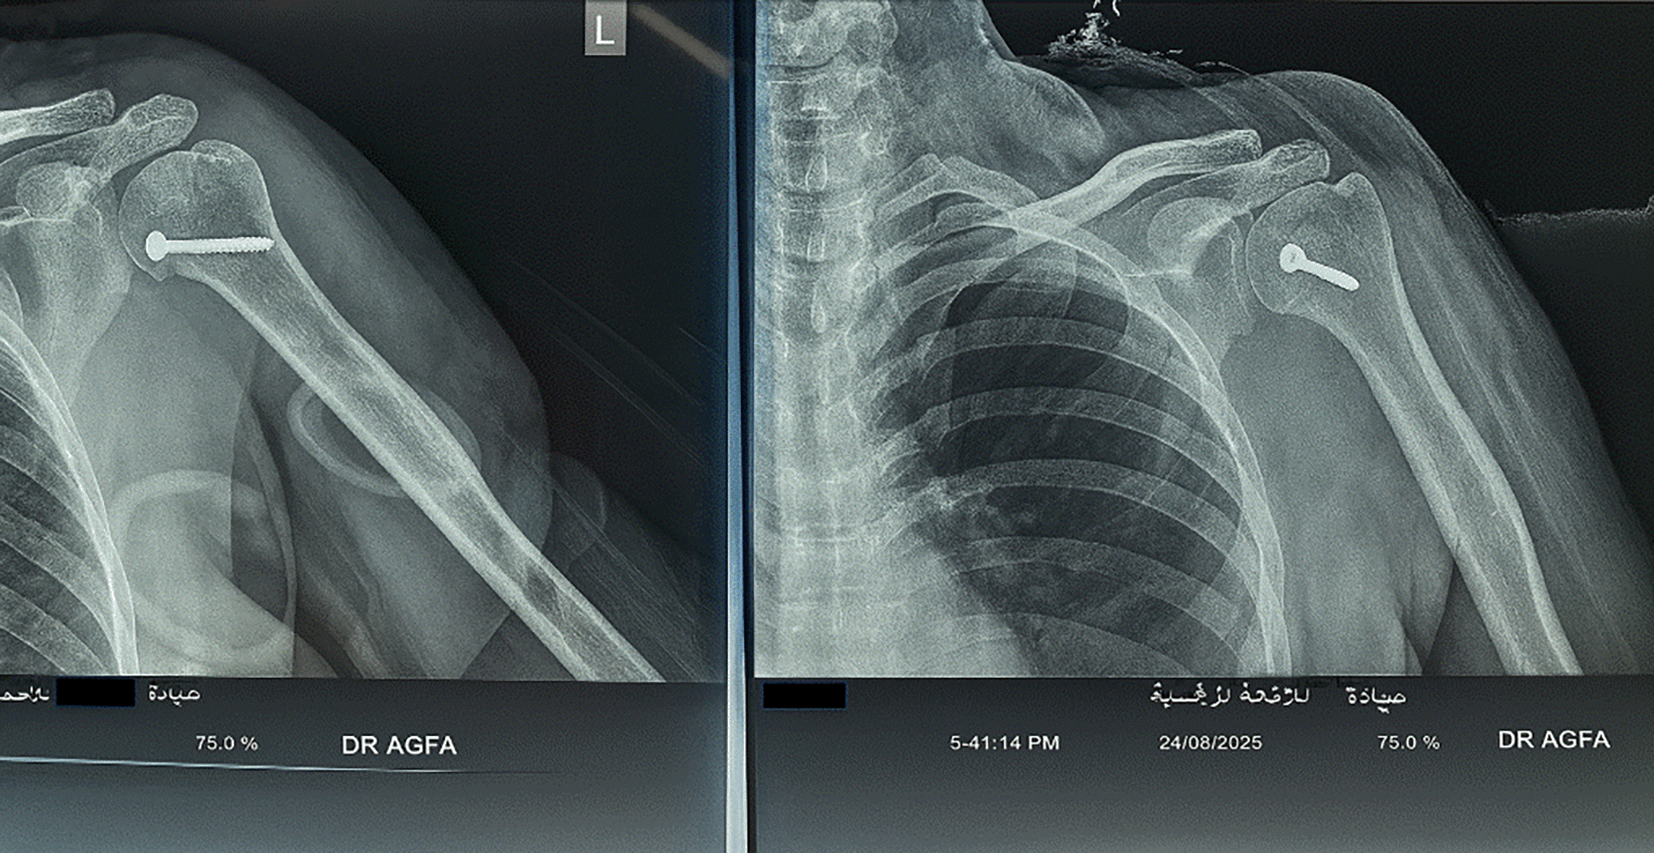

On examination, there was loss of shoulder contour with limitation of movement with a positive posterior drawer test. Radiographs showed a light-bulb appearance ( Figure 1). The CT scan showed Reverse Hillsach lesion ( Figure 2).

On examination, there was loss of external rotation movement of the shoulder. The X-rays showed a light-bulb appearance ( Figure 5). The CT scan: shows Reverse Hillsach lesion ( Figure 6).

The patient was sent for X-rays that showed a light-bulb appearance ( Figure 9). The CT scan showed the impaction of the Humeral Head in the glenoid fossa with an internally rotated Humeral Head that locks the head in situ (inside the glenoid fossa) without exiting the humeral head outside the glenoid socket ( Figure 10).

Radiology included AP, lateral, and axillary views. Computed tomography (CT) scans are required in doubtful cases. Radiological signs included a light bulb appearance, empty glenoid sign (anteroposterior, AP view), or indentation of the anterior part of the humeral head (in Lateral or Axillary view).